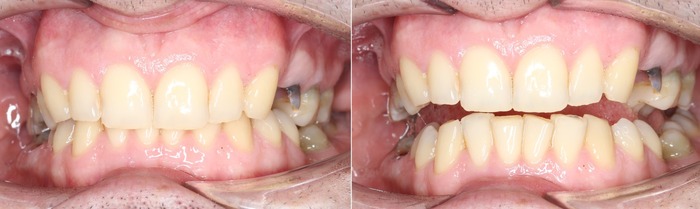

Спустя две недели произведена фиксация временных коронок.

Коронки на имплантатах на нижней челюсти:

Параллельно я удалил два центральных верхних резца, после чего были зафиксированы все остальные временные коронки.

Подчеркну - коронки временные (!), все они будут заменены на постоянные.

Вот так было:

А как стало на промежуточном этапе:

Согласитесь, выглядит очень даже неплохо, если опустить цвет.